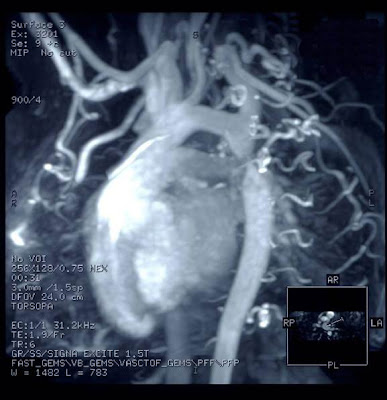

BACKGROUND: MRI is believed to be more sensitive than CT scanning for imaging ischemic stroke, but is considered insufficiently sensitive for acute hemorrhagic stroke.

METHODS: In this single-center study at a suburban hospital in Bethesda, MD, and coordinated at the National Institutes of Health, 356 patients with suspected acute strokes underwent MRI and CT scanning of the brain. The imaging studies were later reviewed by a panel of two neuroradiologists and two stroke neurologists blinded to the patients' clinical findings.

RESULTS: The final diagnosis was acute ischemic stroke in 190 patients (53%), acute intracranial hemorrhage in 27 (8%) and transient ischemic attack in 14 percent. Twenty-five percent of the patients were not ultimately diagnosed with cerebrovascular disease. The sensitivity of CT scanning was 26% for acute stroke overall, 16% for acute ischemic stroke and 89% for acute intracranial hemorrhage (corresponding specificities 98%, 98% and 100%, respectively). The sensitivity of MRI was 83% for acute stroke overall, 83% for acute ischemic stroke and 81% for acute intracranial hemorrhage (corresponding specificities, 97%, 96% and 100%, respectively). In the subgroup of patients imaged within three hours of symptom onset, sensitivities for acute stroke were 27% for CT scanning and 76% for MRI, and specificities were 100% and 96%, respectively.

CONCLUSIONS: Although the authors suggest that their findings are consistent with a superiority of MRI over CT scanning for the imaging of acute stroke, MRI missed more patients with acute hemorrhagic stroke, which could have significant implications when selecting patients for thrombolytic therapy.